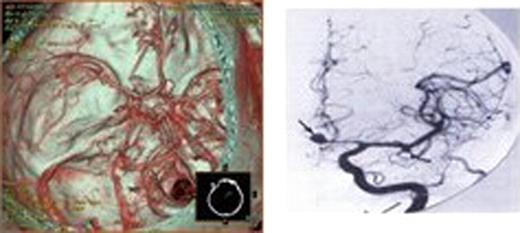

Figure 3:

Magnetic Resonance Imaging(MRI) and CTA revealed rupture of brain aneurysm(Figure 3 A,B).